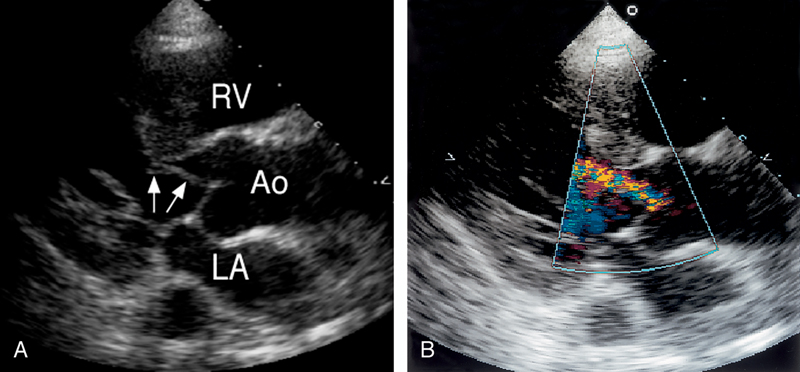

فحوصات تشخيصية لبعض امراض القلب والشرايين التاجية